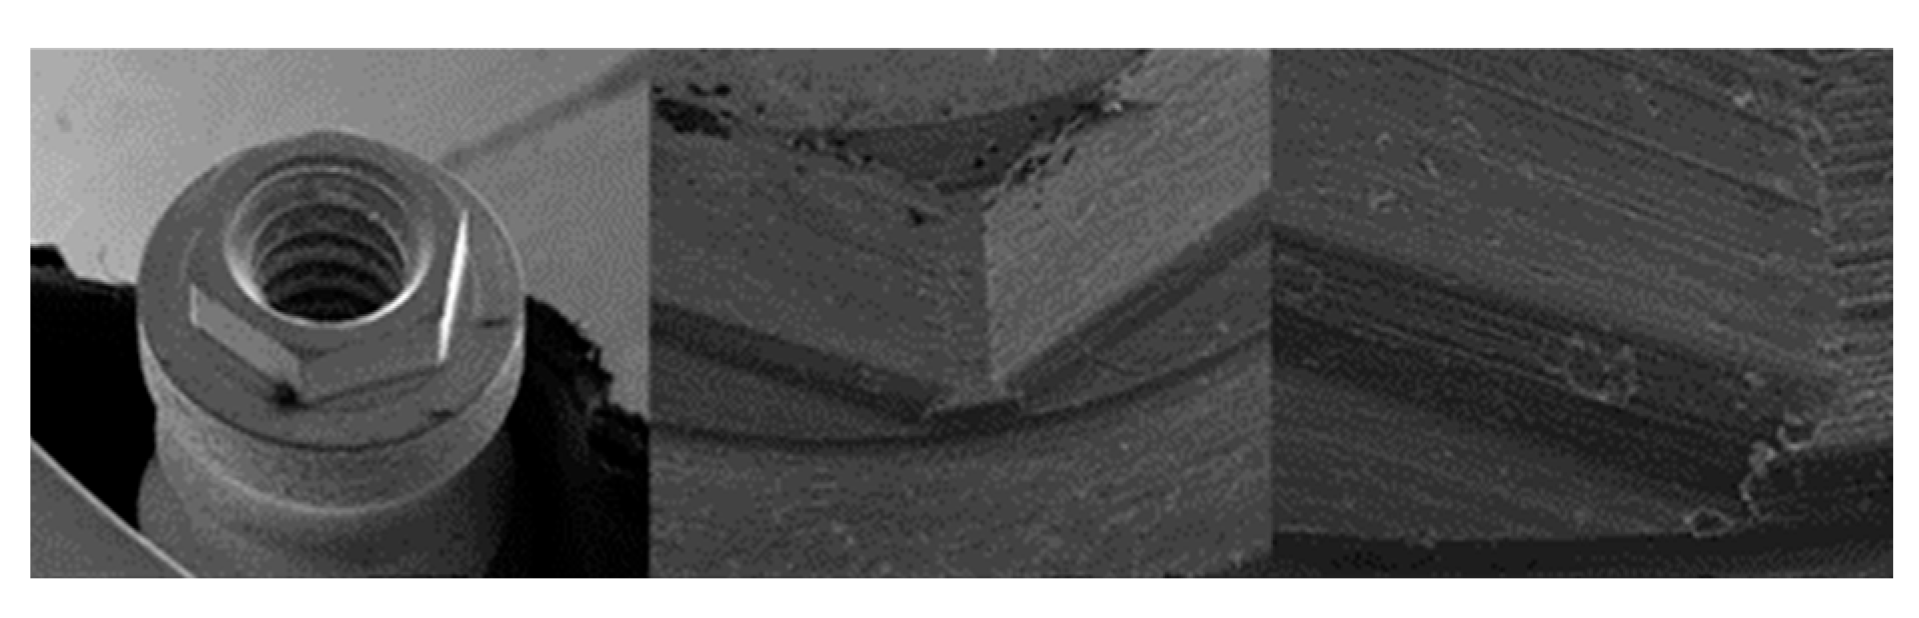

3.1. SEM

3.1.3. SK2 Implants

4.1. SEM Evaluation